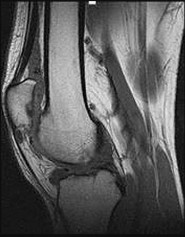

Figures 6a through 6d are the radiographs and T1-weighted sagittal and fat-saturated axial MR images of an otherwise healthy 56-year-old man who has anterior knee pain and intermittent swelling after sustaining a noncontact twisting injury. Low-power and high-power hematoxylin and eosin stained histologic specimens are shown in Figures 6e and 6f. Based on the history, radiographs, CT scan, MR imaging, and histologic findings, what is the most likely diagnosis?

The lesion in the posterior intercondylar knee notch is a benign synovial hemangioma. Intralesional calcifications, classically associated with hemangiomas, are frequently not identified on plain radiographs. The MR imaging reveals a hypervascular lesion with multiple filling defects, with hyperintensity on T2-weighted images and low-to-intermediate signal intensity on T1-weighted images. Histologically, vascular lakes within fine capillaries with a synovium on the surface of the lesion are characteristic of this condition. Many patients with synovial hemangioma have pain, swelling, stiffness, or mechanical symptoms. The correlation of symptoms with the hemangioma for this patient is unclear because there was recent trauma and a concurrent meniscus tear. Simultaneous treatment of both potential sources of pain is typically recommended. As with PVNS, the disease can be localized or diffuse. Surgical excision, either open or arthroscopic, is the recommended treatment. PVNS is the most common intra-articular tumor, but hypointensity in either the diffuse or localized type is characteristic in both T1- and T2-weighted images. Synovial sarcoma, although often found close to a joint, is not characteristically found within a joint.